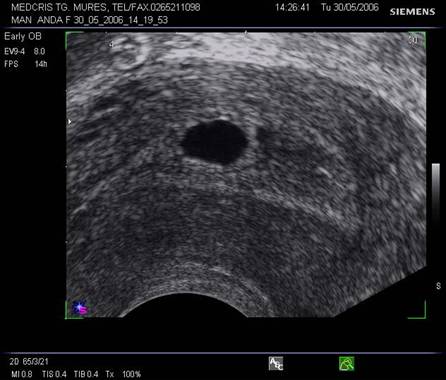

Oul clar este definit ca o sarcina anembrionata si fara sac Yolk (cca 1/3 din avorturile spontane) [10].

Incidenta anomaliilor cromozomiale este mai mare decat la avorturile cu embrion prezent, in special a trisomiilor. Ecografia transvaginala va indica un sac gestational gol, a carui marime este corespunzatoare relativ la durata amenoreei, eventual cu usor contur neregulat.

Pentru a nu face o eroare de diagnostic in prezenta unui sac gestational prea mic , posibil al unei sarcini incipiente, o reevaluare la o saptamana va fi necesara.

Fig. nr. 82 Ou clar la ecografia transvaginala